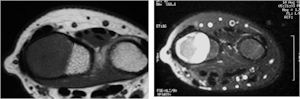

MRI:

- Also useful in determining extent

- There is often extensive edema around the tumor in the surrounding bone and soft tissues that can lead to a misdiagnosis of a malignant tumor.